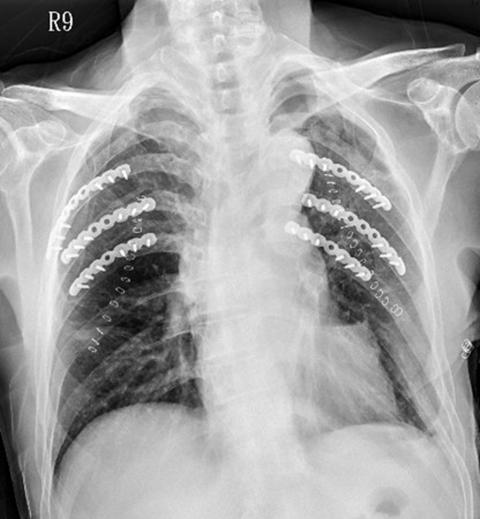

An avid cyclist was out riding with a friend when, trying to evade a small animal that suddenly appeared out of nowhere, he was thrown from his bike. He sustained a broken leg and broken ribs, and air became trapped in his pleural cavity (the space between the chest wall and the lung). He was sent to the emergency room at the Hsinchu branch of National Taiwan University Hospital. One month later the man returned for a follow-up treatment, and told the doctors how happy he was to be able to be riding again.

With improvements in medical treatments and increasing focus on patients’ quality of life, doctors have developed the surgical stabilization of rib fractures. The main objectives of this technique are to reduce the amount of pain the patient with broken ribs is in, to prevent the emergence of complications and to reduce the chance of mortality and the length of stay in hospital. This will help the patient to recover more quickly and to be able to return to work.

According to clinical statistics, the surgical stabilization of rib fractures procedure can significantly lower the chances of the patient developing pneumonia, reduce the treatment period and length of hospital stay by half and even cut the mortality rate by 30 percent.